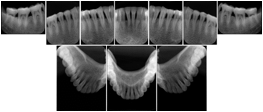

In most standard cases, images are oriented in structured layouts. These structured displays are useful to be shared between providers for reference purposes.

Table OO.1.1-1 shows structured display standard templates, where Viewset ID is based on the Japanese Society for Oral and Maxillofacial Radiology (JSOMR) classification provided by JIRA (Japan Medical Imaging and Radiological Systems Industries Association, www.jira-net.or.jp). Expected or typical teeth to be imaged location, region and designation codes are based on ISO 3950-2010, Dentistry - Designation system for teeth and areas of the oral cavity. For all the hanging protocols listed in OO.1.1-1, the value to use for Hanging Protocol Creator (0072,0008) is "JSOMR" and the value to use for Hanging Protocol Name (0072,0002) does not include "JSOMR" (e.g., "DL-S001A", not "JSOMR DL-S001A").